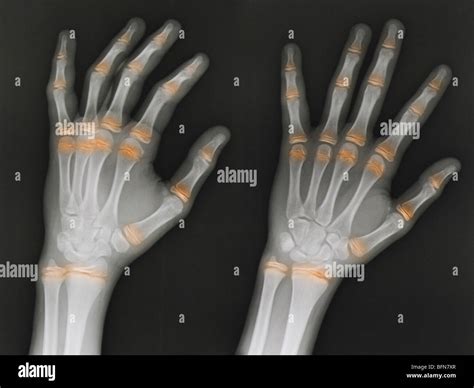

• Arthritis: Hand X Ray can reveal the characteristic bone changes associated with different types of arthritis, such as rheumatoid arthritis and osteoarthritis.

• Joint Spaces: Narrowing of joint spaces can be a sign of arthritis.

Joint Space Narrowing Arthritis